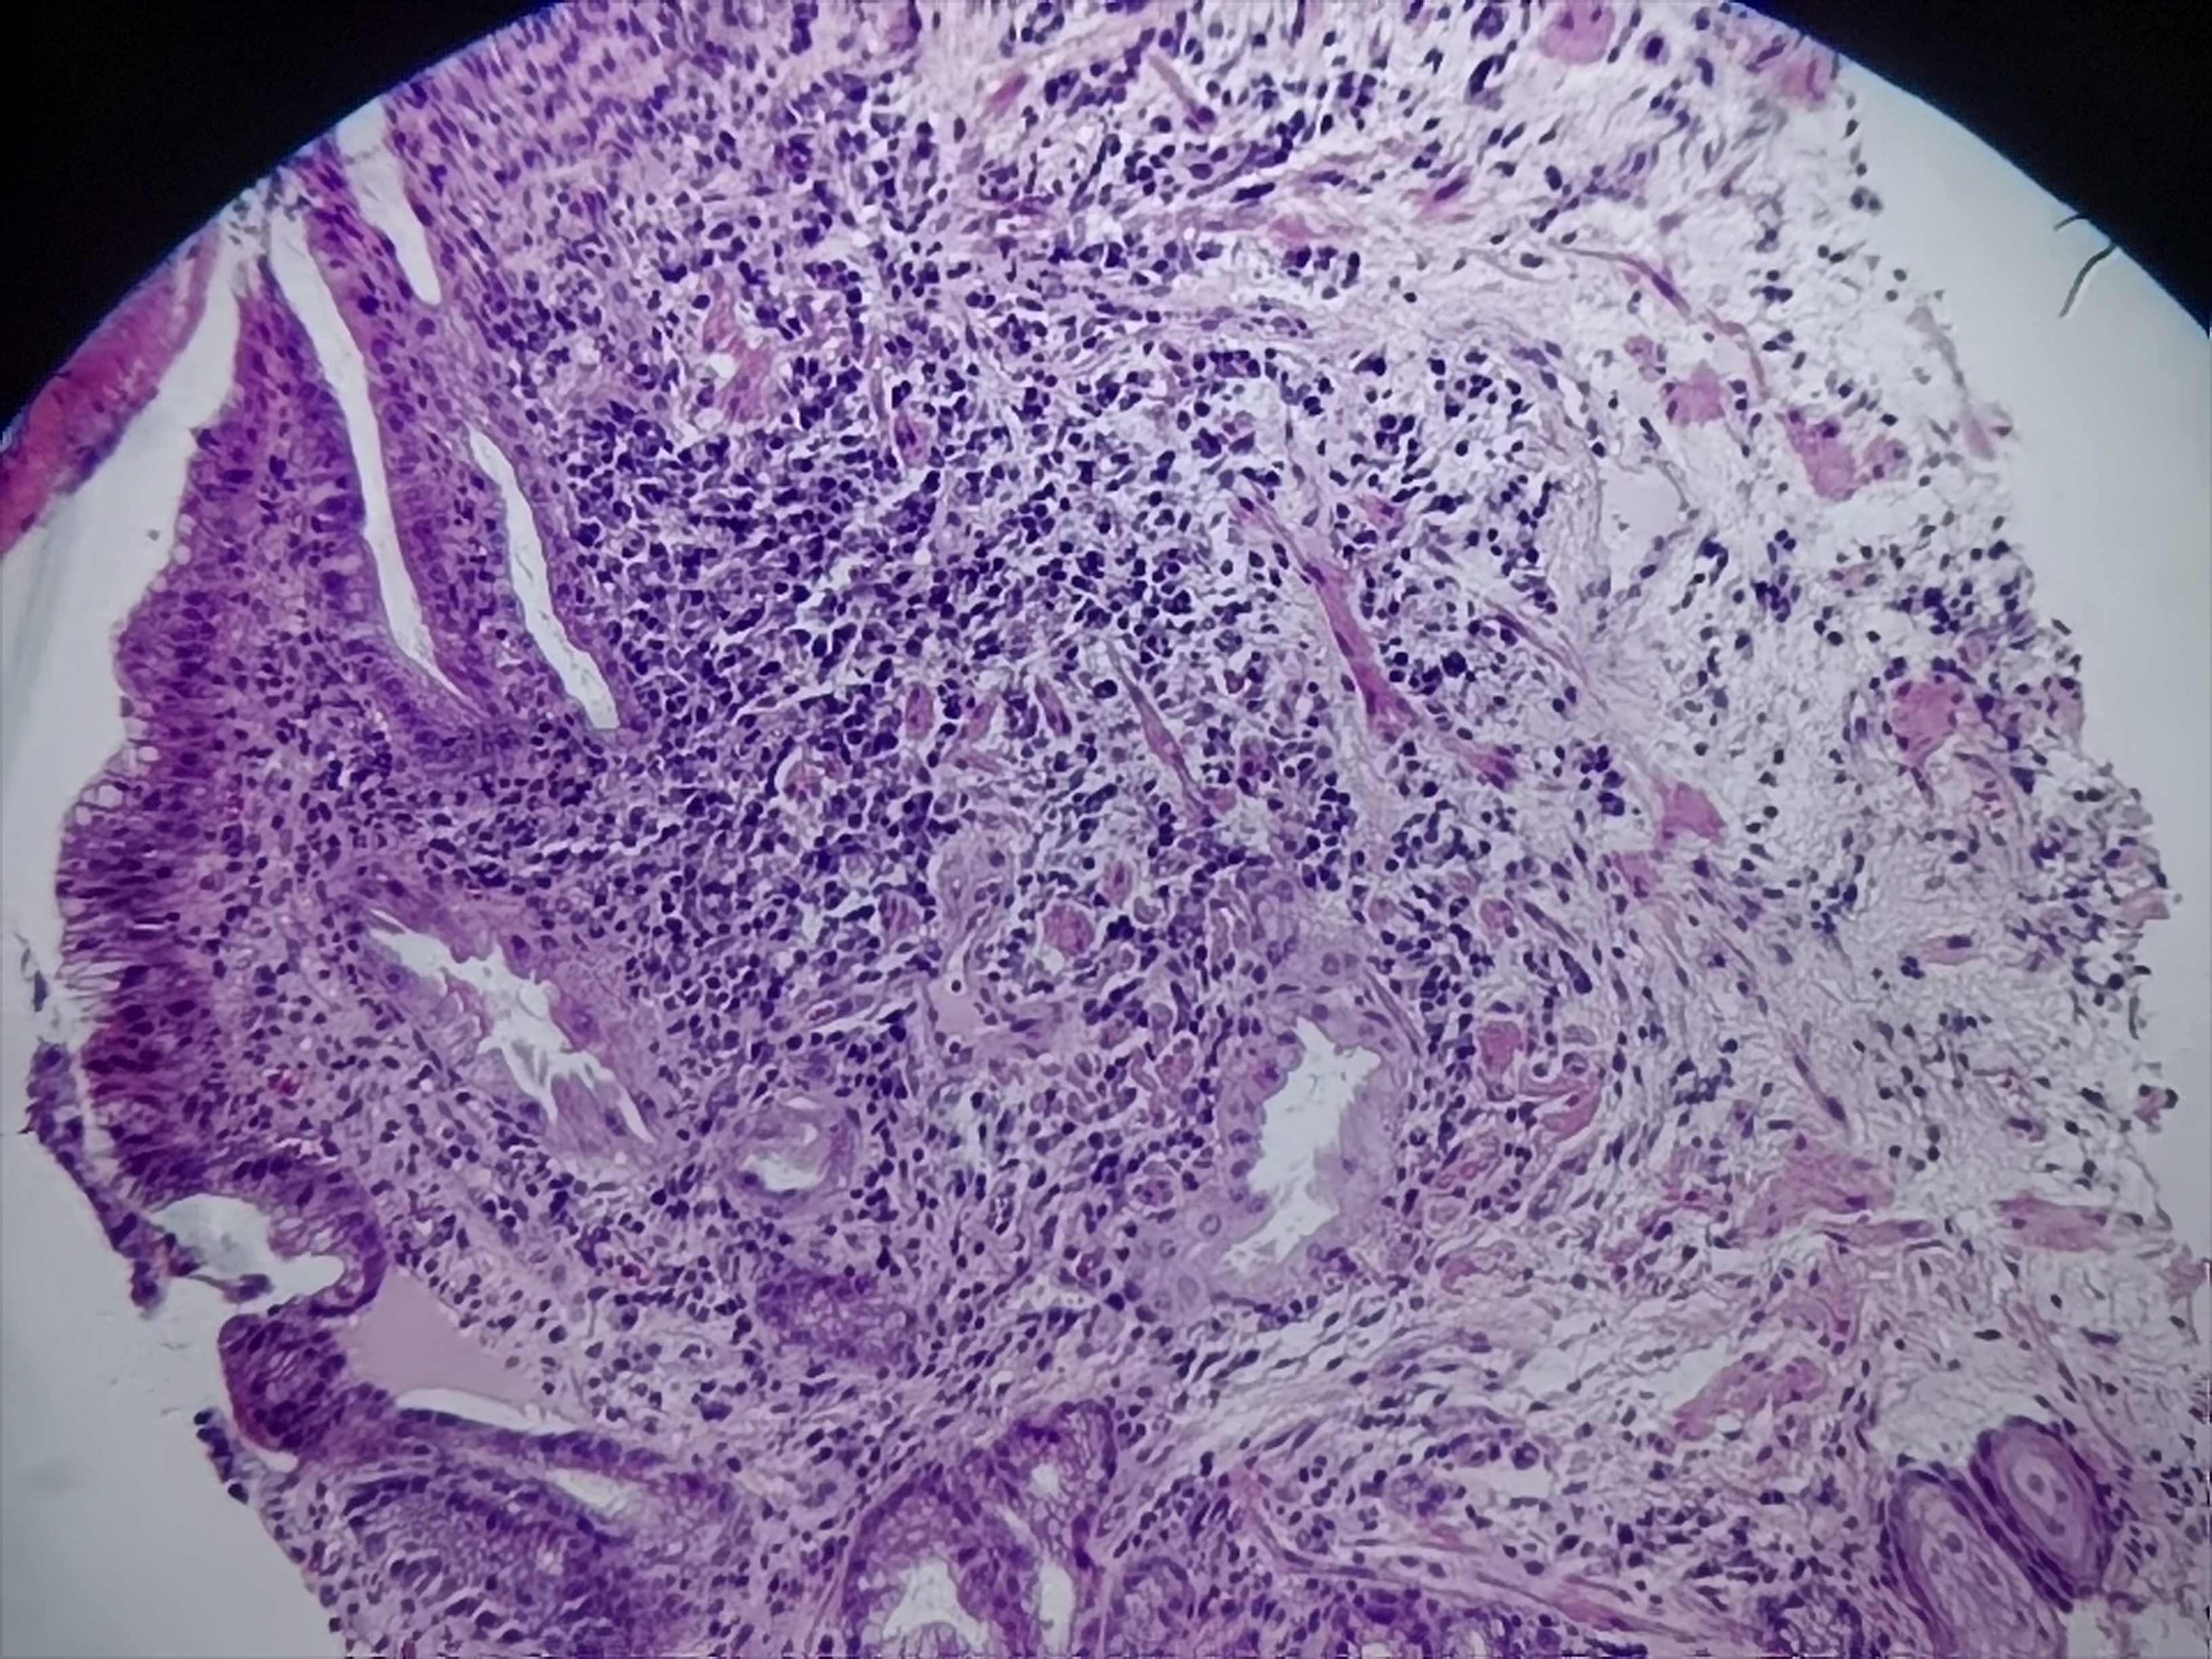

食管活检

性别

男

年龄

58岁

临床诊断

食管术后、反流性食管炎、残胃

一般病史

食管:可见多枚糜烂

标本名称

食管粘膜活检

大体所见

灰白色组织1块

图1

重度慢性活动性炎+糜烂